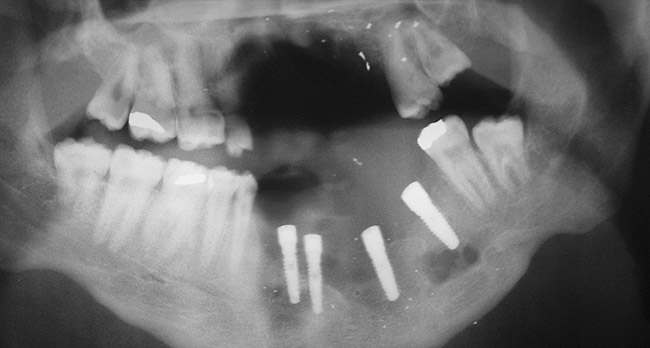

Figure 20a  Panoramic radiograph of a patient who had lost a significant portion of the mandible secondary to trauma.

Figure 20a